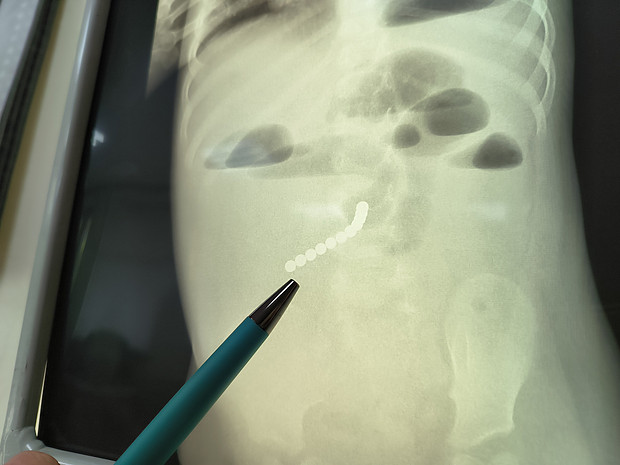

В отделении лучевой диагностики медучреждения проводятся все необходимые виды исследований для выявления и оценки динамики лечения туберкулеза